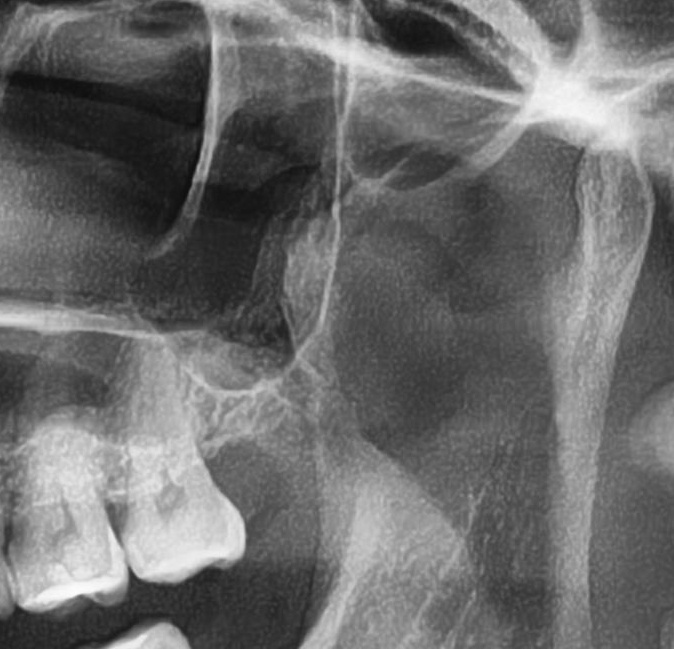

パノラマ写真を撮影してみると、左上の親知らずは歯茎に埋まってはいますが、ほぼまっすぐ生えているのが確認できました。

さらに、上顎の親知らずは上顎洞(副鼻腔)に近接して生えている場合もあるため、CTを撮影して位置関係を詳しく解析します。

上顎の親知らずが上顎洞(副鼻腔)に近い位置に生えている場合や、上顎洞へ突き抜けている可能性がある場合は、大きな病院に紹介する場合もあります。

今回は上顎洞からも距離があるため、抜歯は可能と診断されました。